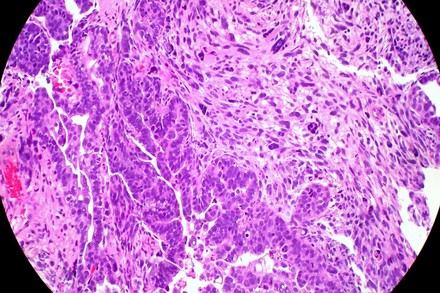

Investigadores de l'Institut de Recerca Biomèdica de Lleida (IRBLleida) i la Universitat de Lleida han identificat el receptor CXCR6 com a possible diana terapèutica per al càncer d'endometri. L'estudi, publicat a la revista Cell Death & Disease, revela que inhibir aquesta proteïna podria frenar la metàstasi en pacients amb formes agressives de la malaltia. Utilitzant models animals i mostres humanes, els científics han demostrat que bloquejar CXCR6 dificulta la migració cel·lular i redueix la càrrega metastàtica. Aquesta investigació obre noves vies per al desenvolupament de teràpies personalitzades i més eficients contra el càncer d'endometri.